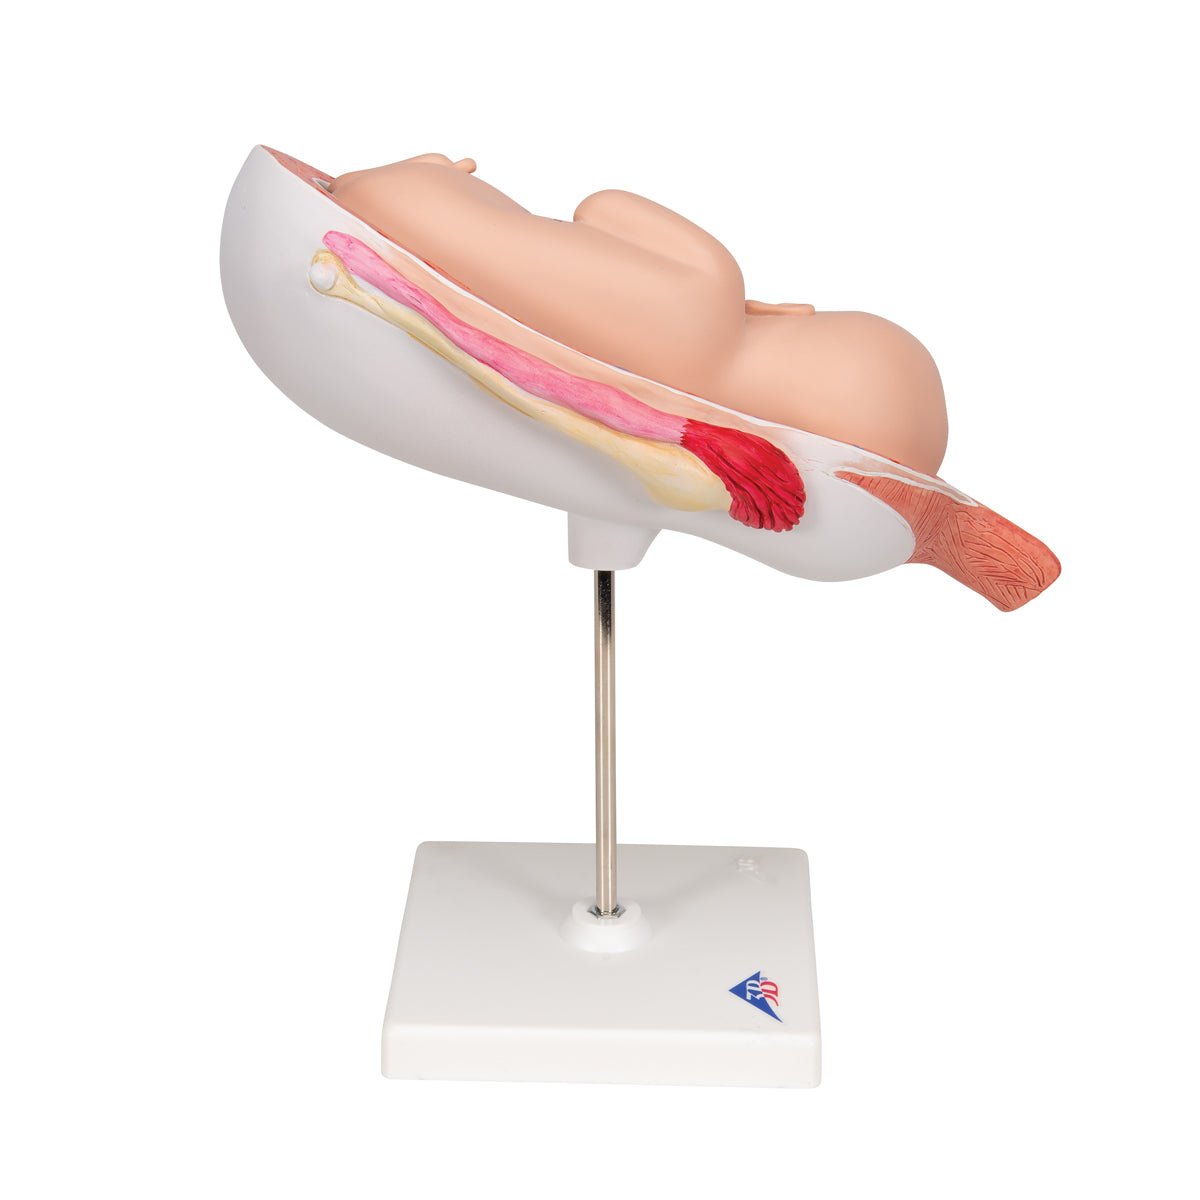

Anatomical models

Selling anatomical models is the mainstay of eAnatomi, although we also spend a lot of resources developing our own anatomical materials such as posters. Anatomical models are used for various purposes and can show both defined tissues, organs and organ systems. Are you looking for a simple model of bone tissue or perhaps an advanced torso model based on MRI technology, you can find it all at eanatomi.com.